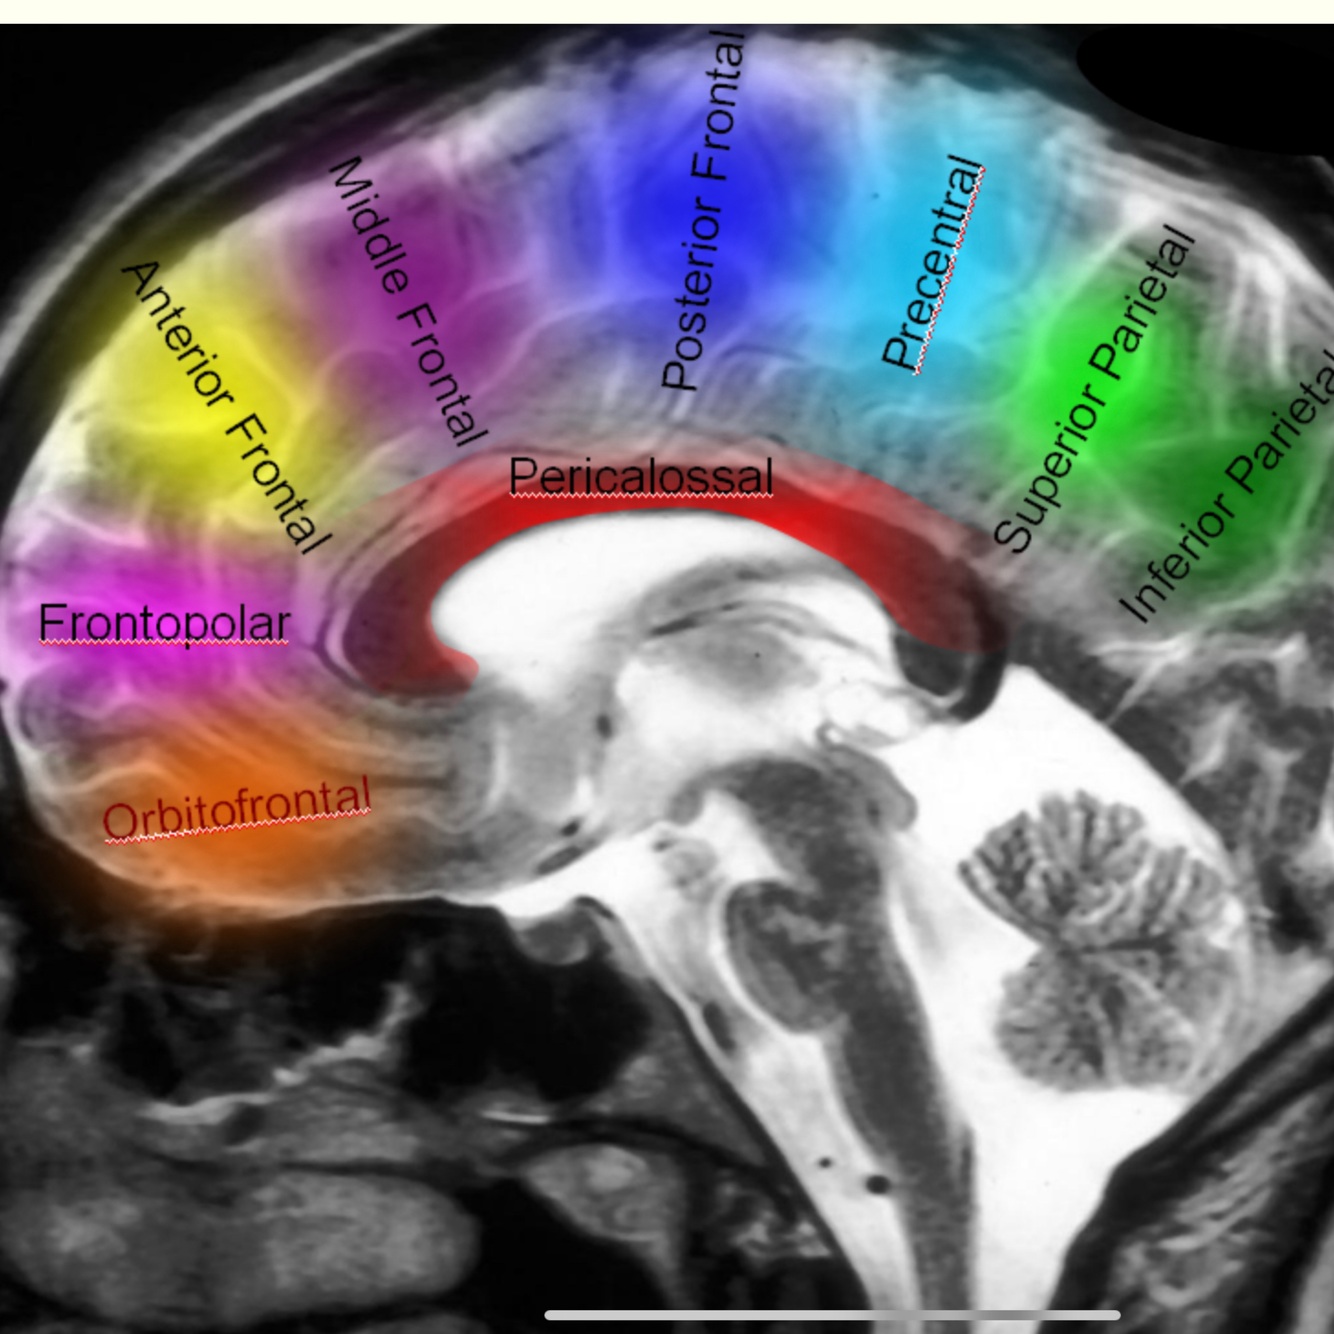

A 1 pre communicating»_space; end ACOM

A2 post communicating > terminate rousting genum junction of corpus collosum

A3 peri collosal > end anterio genum

A4 supra collosal above the body of corpus collosum , anterior Cornoal suture

A5 post collosal terminal end above body of corpus collosum posterior to Cronal suture

Frontopolar

2nd cortical branch

Supply medical frontal pole

Collos marginal

Branches anterio internal frontal ( anterior , middle , posterior )

Paracentral

Preicollosal A5

Superior to genum

Superior internal partial A

Inferior internal partial precuneat A